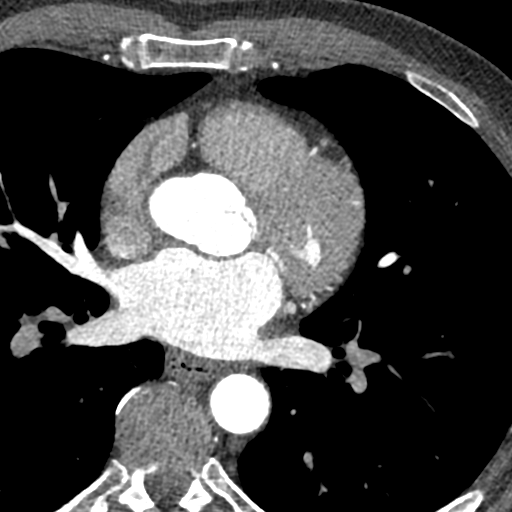

As I mentioned in my prior post there seemed to be a new issue, and the constant scans I have been undertaking over years are a blessing. In 2016 they picked up something out of the ordinary with my celiac trunk*. I needed this like a hole in the head! We let it be for a few years as we had bigger issues to deal with.

However, before I trotted off to chemotherapy we needed some answers. Finally I caught a break, despite the findings the cardiologists recommended: “We discussed the natural history of segmental arterial medial lysis and the finding that this is typically a very low risk recurrence disease. Management would be focused around continued heart healthy lifestyle choices such as daily exercise, heart healthy dietary choices, and adequate sleep. Beyond this, I do not think any further intervention is warranted other than observation.“

*The celiac artery, also known as the celiac axis or celiac trunk, is a major splanchnic artery in the abdominal cavity supplying the foregut. It arises from the abdominal aorta and commonly gives rise to three branches: left gastric artery, splenic artery, and common hepatic artery.